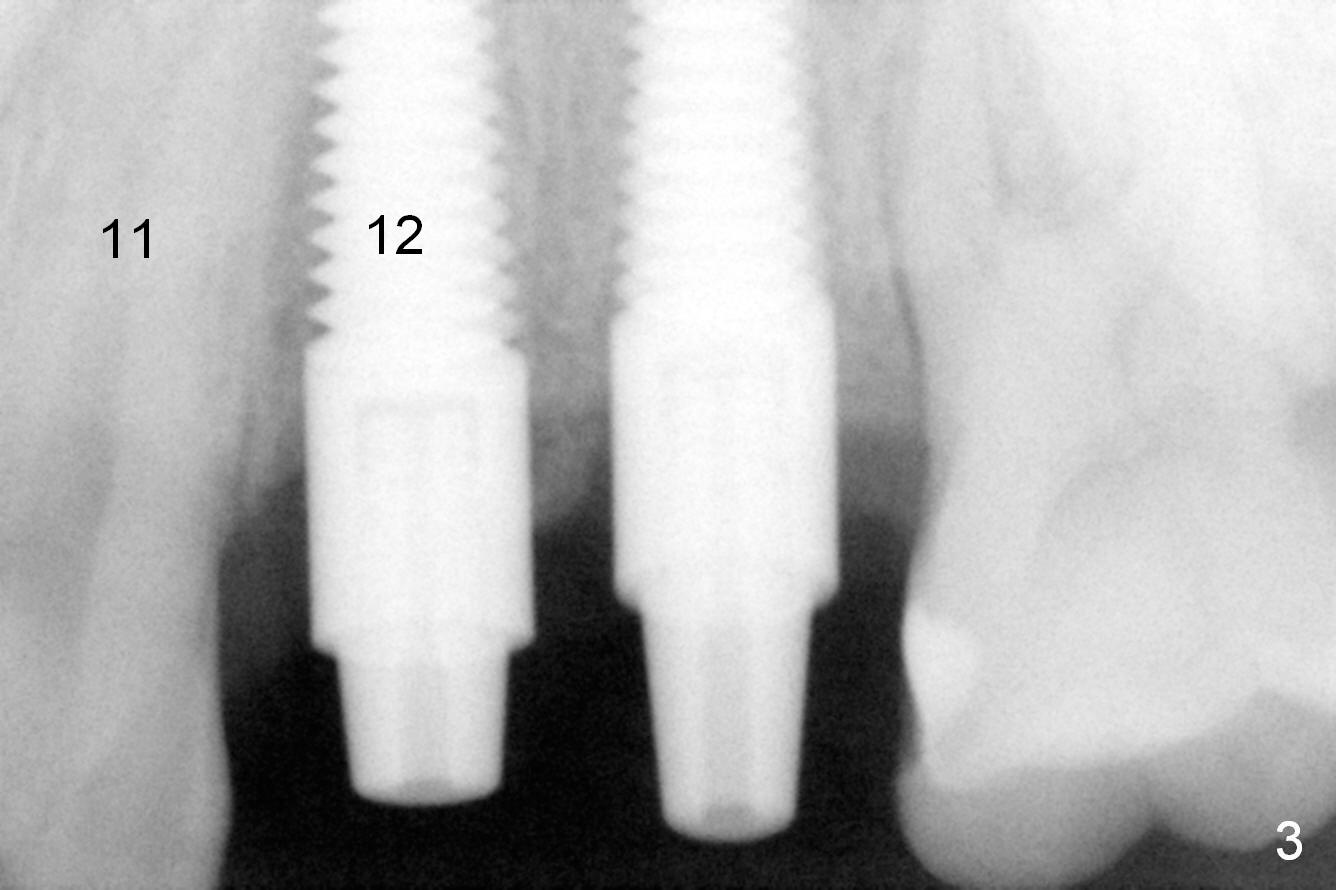

Taking 2 additional PAs with sensor 1 is frustrating (Fig.1,2), no apices shown.  Osteotomy is done smoothly with 2 mm pilot drill at 20 mm, 2.5 mm reamer at 17 mm, and 3 mm reamer at 14 mm and 4.5x20 mm tap at 17 mm.  The 1st intraop PA is taken with sensor 1 when 2 of 4.5x20 mm implants are placed (Fig.3); the implant at #12 is close to the root of the tooth #11.  The 2nd PA is taken with sensor 2: the apex of #11 touches the implant at #12 (Fig.4).  There is no separation when panoramic X-ray is taken (Fig.5).  Effort is exerted to re-direct the osteotomy twice (Fig.6: tap; Fig.7: implant) without success.  When the implant is removed, a PA is taken; it appears that the root of the tooth #11 has no damage (Fig.8).  To obtain the best recovery, socket preservation is carried out with 50/50 cortical/cancellous allograft mixed with Osteogen (Fig.12 *) and Collagen Dressing (Fig.9: #12).  A 2 (or 3)-unit provisional bridge (Fig.10: #12,13) is fabricated over the implant (Fig.9 I)/abutment (A) to cover these 2 sockets.  After acid etching #11 D surface (Fig.9 >) and relining (Fig.11 *), the provisional bridge is bonded to the tooth #11 (Fig.11,12 black >) so that bone graft will be less likely dislodged.